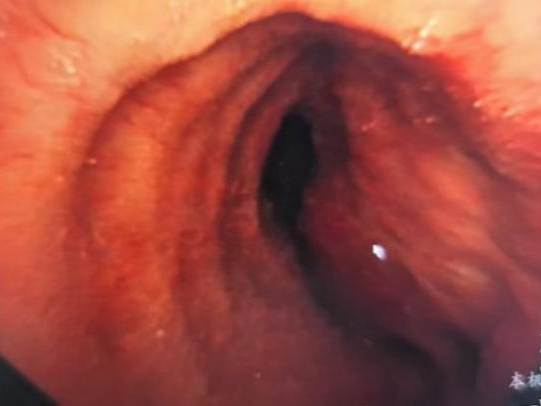

入院时,王大爷已经面色青紫、呼吸艰难、三凹征明显,支气管镜下探查及活检结果显示,主气道重度狭窄且病变累及右侧主干,伴原发性肺鳞癌。